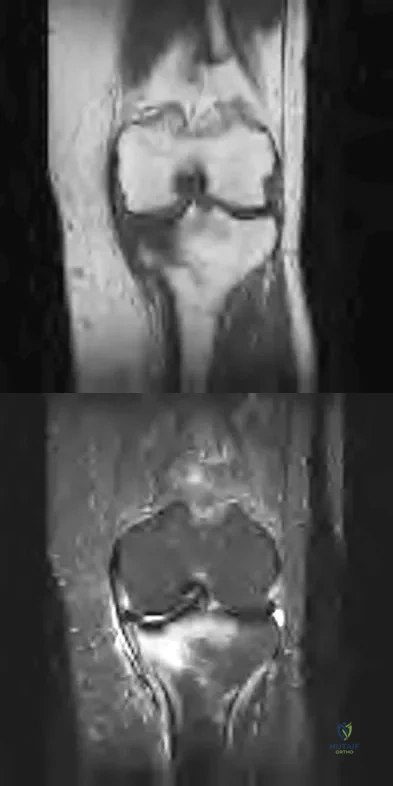

A 28-year-old man reports knee stiffness, swelling, and a constant ache that is worse with activity. Examination reveals an effusion, global tenderness, and warmth to the touch. Flexion is limited to 110 degrees. Figures 48a through 48d show sagittal T1-weighted, sagittal T2-weighted, axial T1-weighted fat-saturated gadolinium, and axial gradient echo MRI scans. Based on these findings, what is the most likely diagnosis?

Explanation

The MRI scans show multiple low-signal intensity lesions scattered throughout the knee, extending posteriorly inferior to the tibial plateau. The low-signal intensity on both the T1- and T2-weighted images, the modest vascularity noted on the gadolinium image, and the "blooming" noted on the gradient echo image (ferrous-laden tissue) are all strongly suggestive of diffuse PVNS. Whereas synovial chondromatosis can present as diffuse masses in the knee, they present as nodule masses that have low T1- and high T2-weighted signal characteristics. Resnick D (ed): Diagnosis of Bone and Joint Disorders. Philadelphia, PA, WB Saunders, 2002, pp 4241-4252.

References:

- Sanders TG, Parsons TW: Radiographic imaging of musculoskeletal neoplasia. Cancer Control 2001;8:1-11.